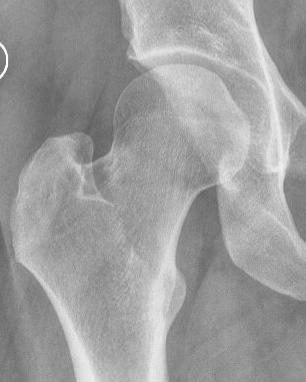

Bilateral pincer

Ossified labrum

Os acetabuli